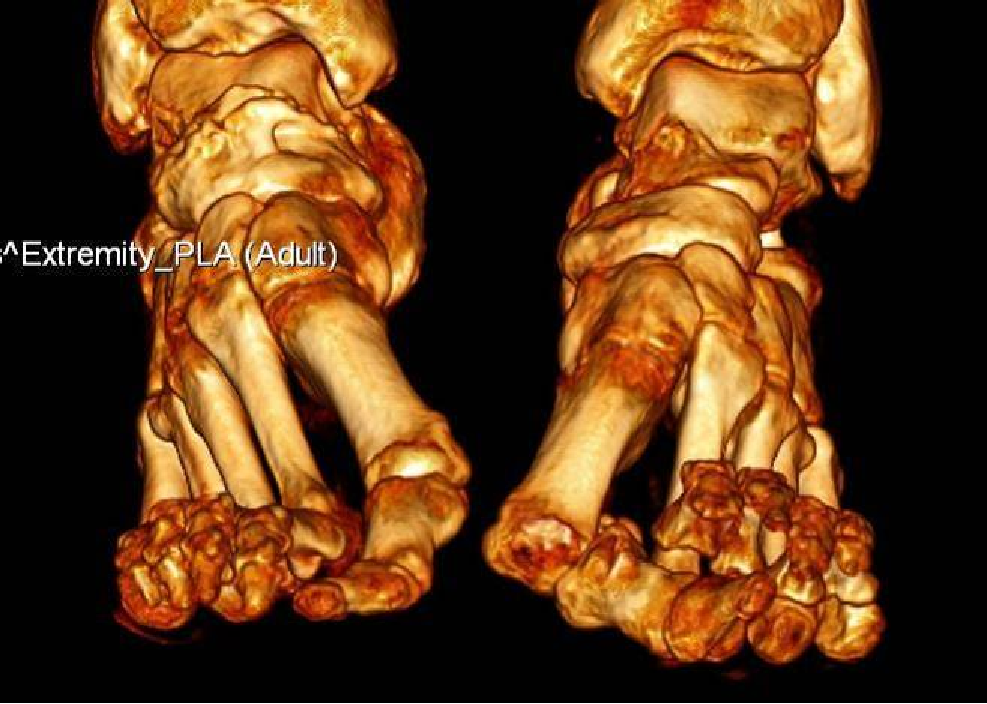

典型病例例1:姚X,女,78Y。

Chevron+第二跖骨Weil

CT重建:第1跖骨头破坏。

术式:左足:第1跖趾关节融合+第2-5跖趾关节成形术;右足:第4趾间关节融合+第5跖趾关节成形术